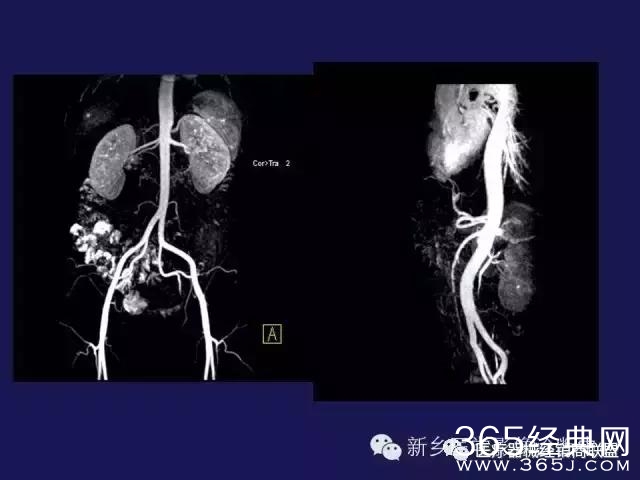

CT、MRI很难?NO,今日我们一起来学习一下如何读CT、MRI!

内行看门道:

整整90张图